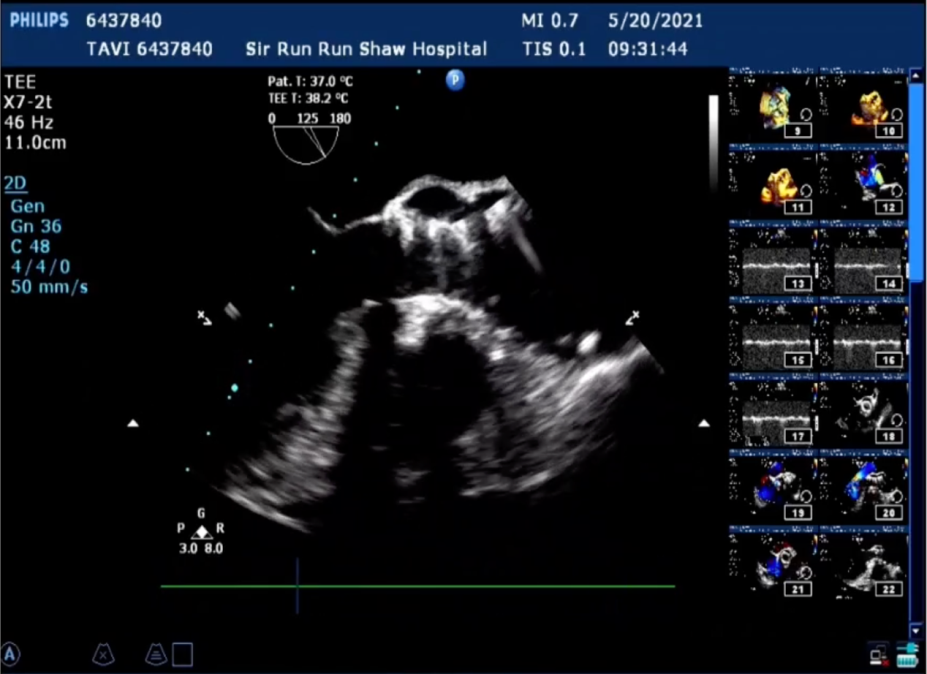

术后心电监护未见传导阻滞。术后超声显示右冠和无冠交界处少量瓣周漏,人工瓣膜工作良好,瓣叶启闭正常,主动脉瓣峰值流速2.36m/s,平均跨瓣压差较术前显著下降为14.3mmHg,手术圆满完成。

经食道左室长轴切面显示瓣架高度处0位